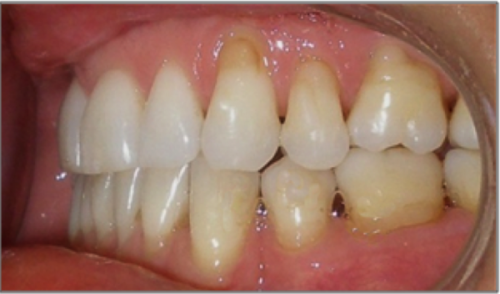

44 year old female:

Diagnosis:

- Upper and lower arch collapse due to missing teeth

- Retrusive angulation of upper & lower front teeth

- Severe collision and wear of front teeth